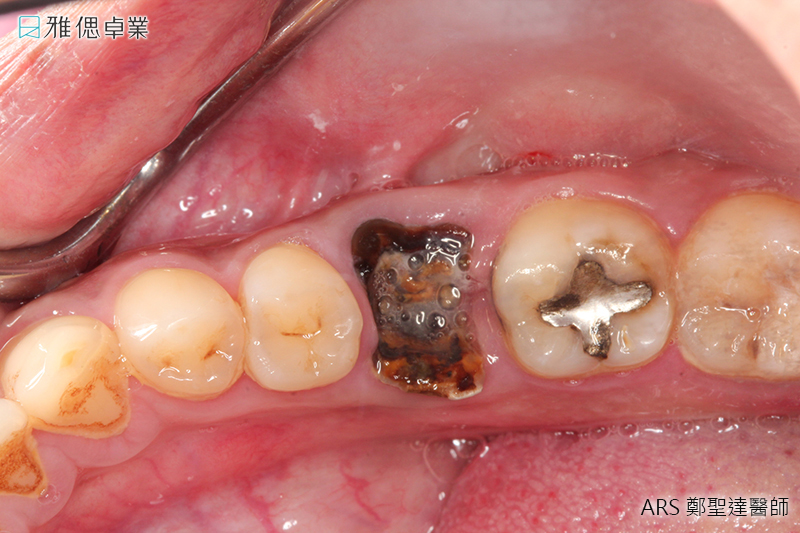

STEP2 植入人工植牙手術

局部麻醉後,醫師會利用手術導引板抓取精準位置與角度,將植體放入齒槽骨中,先進的數位導引板不僅能縮小手術誤差,同時也可控制傷口範圍,使植牙術後的癒合更為迅速。植入人工牙根後,骨細胞就開始進行植體的整合。